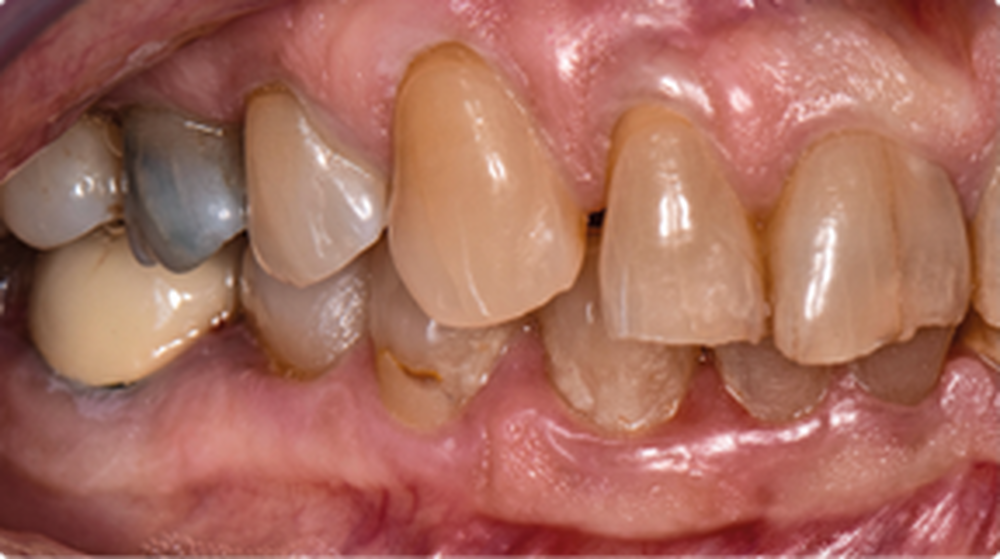

Une patiente…